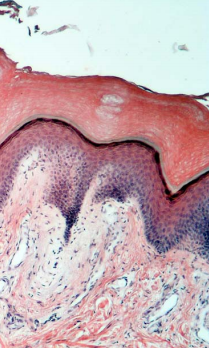

1. Espophagus

Has all 5 layers… espeically stratum lucidum which means its thick skin

stratified squamous keratinized epithelium